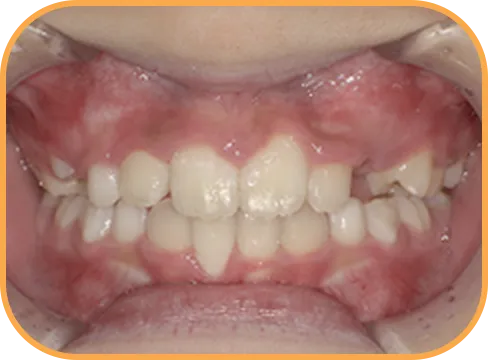

• Before

• 正 面

治療前正面からの歯の様子

主 訴

上の前歯がねじれている、ガタガタ

治療内容

インビザライン・ファースト

治療期間

8か月

治療費(税別)

450,000円+診断料50,000円

リスク・副作用

• 親知らずの影響や加齢などによって、凸凹が生じる可能性があります。

• 治療の初期段階では痛みや不快感が生じやすくなりますが、1週間前後で慣れます。

• 顎の成長発育によって、噛み合わせや歯並びが変化する可能性があります。

• 状況により当初予定した治療計画を変更する可能性があります。